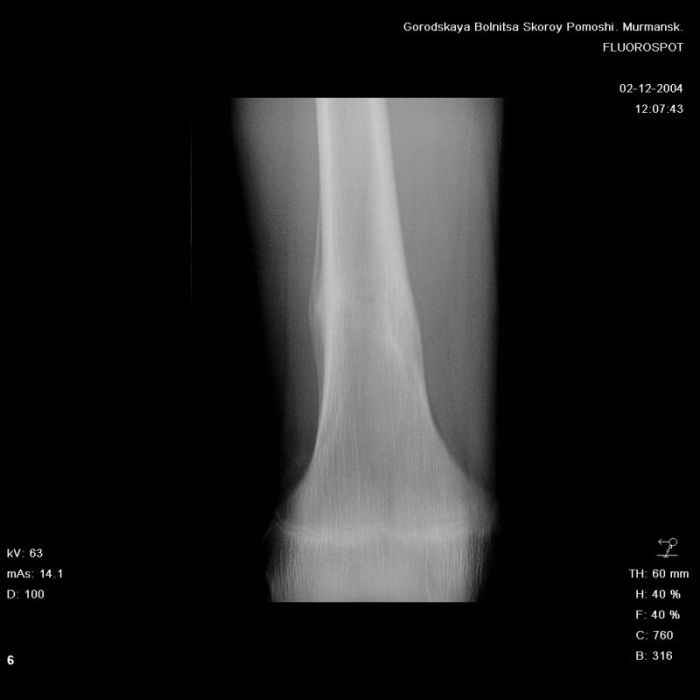

Здравствуйте, уважаемые коллеги!Представляю вашему вниманию интересный случай и пока что непонятный для меня в диагностическом плане. На днях в наше отделение (детской ортопедии и травматологии) поступил 13-летний мальчик по направлению из поликлиники с диагнозом: остеома нижней трети правого бедра.

Анамнез практически никакой: в следствие травмы (растяжение связок коленного сустава) от 07.11.2004 выполнены Rg-граммы в травмпункте и обнаружено опухолевидное образование. Первичные Rg-граммы я не публикую, так как они заметно худшего качества, да и динамики за прошедшие три недели не отражают. Болевой синдром купирован в течение трёх дней. В настоящий момент мальчика ничего не беспокоит. Ходьба не нарушена, опухоль пальпируется с трудом по задней поверхности в н\3 правого бедра, пальпация безболезненна, объем движений в суставах правой нижней конечности полный и симметричный. Кожа над опухолью не изменена.В нашей клинике проведено дополнительное обследование: общие анализы крови и мочи, биохимия крови без особенностей. Выполнены Rg-граммы на цифровом Siemens обычные и продольные томограммы срезами 3-5 мм, а также компьютерная томография поперечными срезами по 5 мм. Прошу обратить внимание, что на приведённых томограммах видны две полости 10х15 мм и 15х60 мм. Также имеются два опухолевидных образований наслаивающихся друг на друга: уплощённое и вытянутое 10х100 мм и элипсовидной формы 15х30 мм. Это хорошо заметно на фото a_1.jpg c_1.jpg и d_1.jpg. Плотность внутри полостей 125% от плотности костномозгового канала, плотность наружного опухолевидного образования 55% от плотности кортикального слоя. Также отмечается линия перелома по центру наружного опухолевидного образования.Исходя из полученных данных мнения в плане диагноза несколько разделились от 1)сочетания кортикальной фиброзной дисплазии и латентно протекавшего маршевого перелома н\3 правого бедра до 2)остеосаркомы. В отношении первого варианта не сходится отсутствие клиники при переломе такой крупной кости как бедро, второй вариант вообще оставлю без комментария, ибо некомпетентен. Хотелось бы услышать мнения коллег, с удовольствием ознакомлюсь с любыми предположениями и замечаниями.С уважением, Александр Е. КлоковОтделение детской ортопедии и травматологииБСМП г. Мурманска.